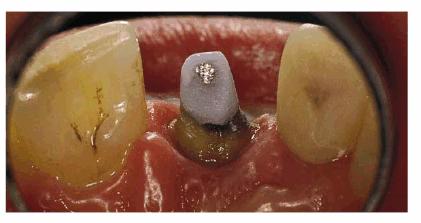

concept is supported by most studies. Such a patient can be seen in Figur 323s1823d es 18-10A 18-10B to G, and 18-10H. Post restorations used in anterior

Figur 323s1823d e 18-10A: This young lady fractured her left central and lateral incisors in an accident. Because the original teeth had protruded before fracturing, the patient requested that the restoration be accomplished with an improved appearance in the most permanent treatment available.

Figur 323s1823d e 18-10B to G: Following endodontic therapy, two cast posts were constructed and cemented to place in the prepared incisors.

Figur 323s1823d e 18-10H: The final all-ceramic crowns were bonded to place. Note the natural result of both the shade and texture of the crowned teeth.